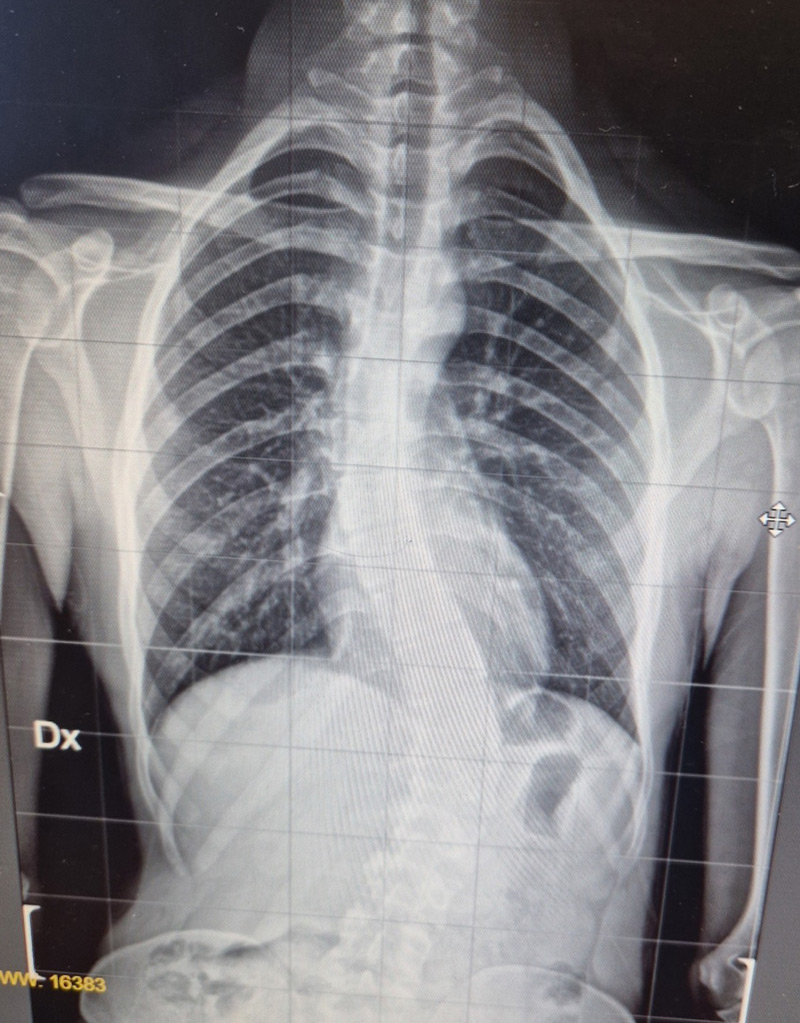

DIAGNOSI:

Scoliosi dorso lombare

Radiografia della colonna in toto pre-operatoria